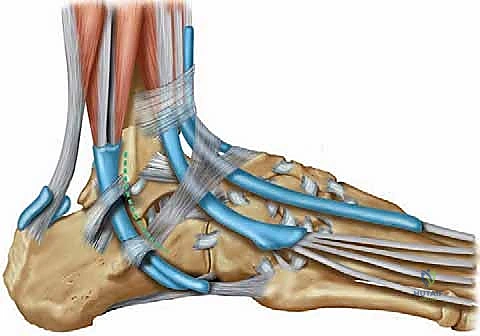

الخطوة 2: استخراج وتر العضلة الأخمصية (Graft Harvesting)

من خلال شق صغير جداً في الجزء الخلفي من الساق، يقوم الدكتور هطيف باستخدام أداة خاصة (Tendon Stripper) لاستخراج وتر العضلة الأخمصية بدقة فائقة دون الإضرار بالأنسجة المحيطة. يتم بعد ذلك تنظيف الوتر وتجهيزه وتحديد طوله المناسب ليصبح الرقعة المثالية.

الخطوة 3: الوصول إلى المفصل وإزالة الأنسجة التالفة

يتم عمل شق جراحي مقوس على الجزء الخارجي من الكاحل. يقوم الجراح بكشف العظام (الشظية، الكاحل، الكعب) وإزالة بقايا الأربطة الممزقة والمتهالكة، وتنظيف المفصل من أي نتوءات عظمية أو التهابات مزمنة.

الخطوة 4: حفر الأنفاق العظمية (Bone Tunnels)

هذه هي المرحلة الأكثر دقة. باستخدام أدوات حفر دقيقة (Drill Guides) موجهة بالأشعة داخل غرفة العمليات، يقوم الدكتور هطيف بحفر أنفاق صغيرة جداً في المواقع التشريحية الدقيقة لمرتكزات الأربطة الأصلية:

* نفق في عظمة الشظية (Fibula).

* نفق في عظمة الكاحل (Talus) لتعويض رباط ATFL.

* نفق في عظمة الكعب (Calcaneus) لتعويض رباط CFL.

الخطوة 5: تمرير الوتر وتثبيته (Graft Passage & Fixation)

يتم تمرير وتر العضلة الأخمصية عبر هذه الأنفاق العظمية بطريقة هندسية تحاكي شكل الأربطة الطبيعية (غالباً على شكل حرف V أو Y). بعد تمرير الوتر، يتم ضبط درجة الشد بدقة متناهية؛ بحيث لا يكون الكاحل مشدوداً جداً (مما يعيق الحركة) ولا مرتخياً (مما يعيد عدم الاستقرار).

يتم تثبيت الوتر داخل الأنفاق العظمية باستخدام مسامير تداخلية قابلة للامتصاص (Bioabsorbable Interference Screws) أو خطاطيف معدنية دقيقة (Suture Anchors). هذه المواد توفر تثبيتاً فورياً وقوياً يسمح ببدء التأهيل المبكر.